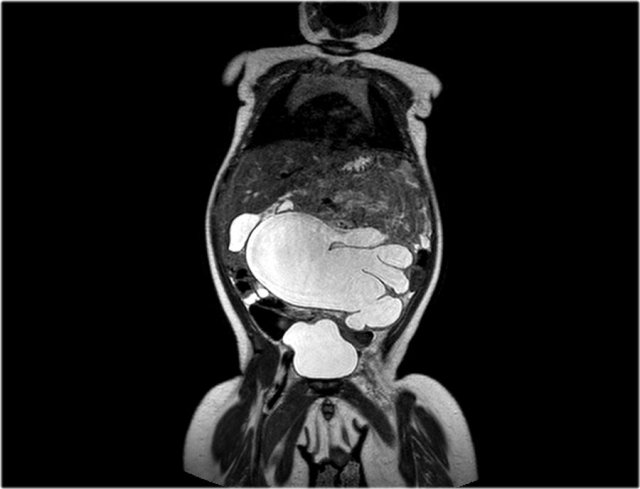

here an one and a half year old girl with a palpable tumor in the left abdomen.

Ultrasound showed a large tumor composed of innumerable cysts, originating from the left kidney.

On a T2 weighted coronal image the cysts are well displayed.

The remainder of the left kidney is at the caudal side of the tumor.

On pathology a cystic partially differentiated nephroblastoma was diagnosed.